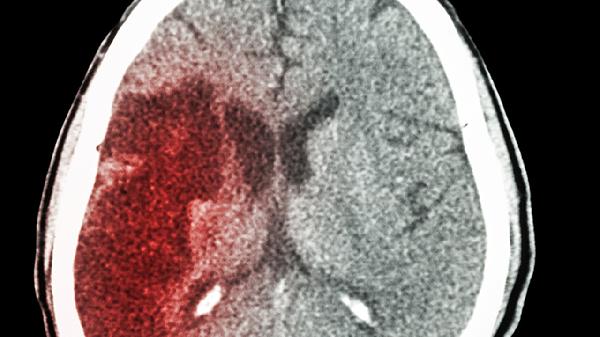

脑出血后血肿直接压迫周围脑组织,或继发脑水肿使颅内压力急剧升高,可能迫使部分脑组织向压力较低区域移位。常见如小脑幕切迹疝,表现为意识障碍加深、瞳孔不等大及对侧肢体瘫痪;枕骨大孔疝则可能突发呼吸心跳骤停。这类情况多发生于出血量大、部位深或未及时干预的患者中。

部分脑出血患者因出血量较小、位置表浅或及时接受降颅压治疗,可能避免脑疝发生。例如壳核出血量小于30毫升且水肿控制良好时,脑疝风险显著降低。但需警惕迟发性脑水肿或再出血导致的继发脑疝。